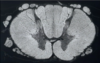

Review of Spinal Cord - Transverse Section

- Grey matter confined to inside and subdivided into regions:

- Dorsal grey horn

- Receives sensory fibres

- Many synapses occur here

- Lateral grey horn

- Contains preganglionic visceral neurons

- Ventral grey horn:

- Contains motor somatic neurons

- Dorsal grey horn

- White matter on outside –> this is where we will find the sensory and motor pathway

- Dorsal white column

- Lateral white column

- Ventral white column

- Ventral white commissure

- Allows fibres to cross from either side

Are the sensory and motor pathways found in grey or white matter?

White matter